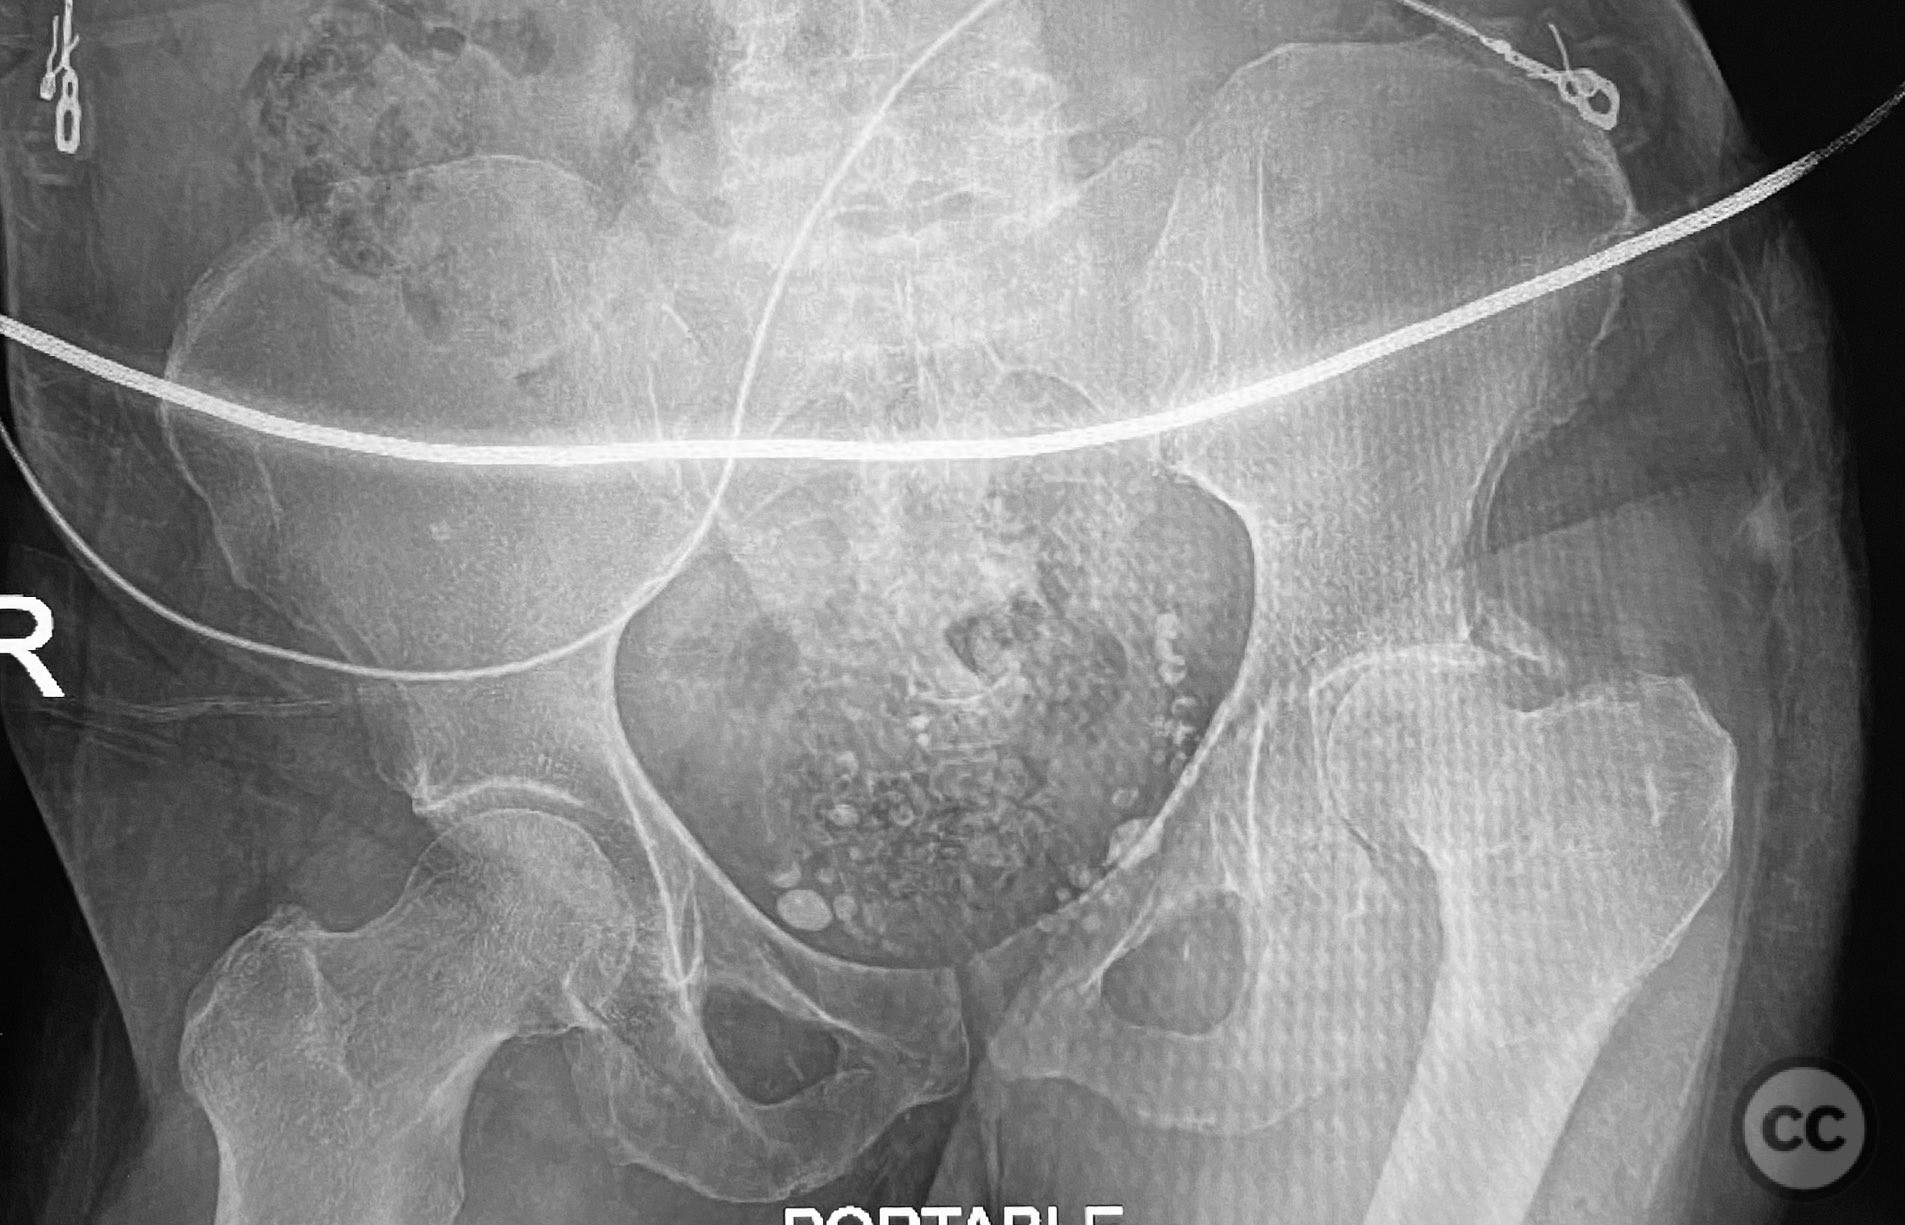

Clinical and radiological findings:  A patient sustained a posterior wall acetabular fracture-dislocation, characterized by comminution of the posterior wall, impaction of fragments into the posterior column region, and intra-articular loose fragments within the fossa acetabuli. Sagittal imaging demonstrated femoral head impalement on the intact wall, raising concern for potential irreducibility. Coronal and axial CT images revealed acetabular and femoral head impactions, peripheral wall comminution, incomplete fracture extension at the acetabular notch and quadrilateral surface, and an articular fragment within the joint. Surface renderings confirmed the extent of peripheral wall comminution and impaction. Despite these findings, a closed manipulative reduction was successfully achieved, resulting in a congruent reduction on post-reduction imaging.

Preoperative Plan

Planning remarks:  The preoperative plan included a prone Kocher-Langenbeck (KL) approach to the acetabulum. The plan involved application of a distractor to facilitate removal of intra-articular loose fragments, elevation of impacted articular segments, bone grafting of resultant defects with ground allograft, and stabilization of the posterior wall with multiple plates, including a custom spring hook plate for peripheral fragment support.